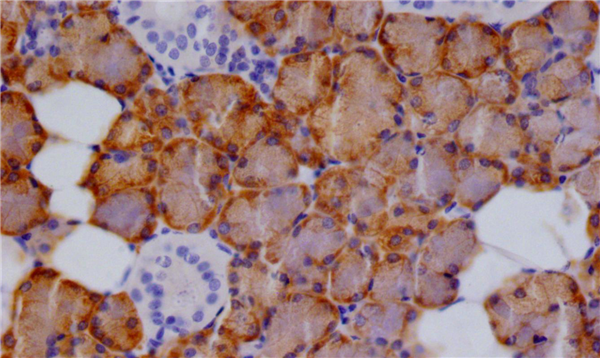

IHC圖像

CTPS1重組單克隆抗體以1:100稀釋度在石蠟包埋的人類唾液腺組織中染色,實(shí)驗(yàn)在Leica BondM系統(tǒng)上進(jìn)行。在脫蠟和水化后,抗原修復(fù)通過在pH 6.0的檸檬酸緩沖液中高壓處理完成。切片用10%正常山羊血清在室溫下封閉30分鐘,然后用1% BSA稀釋的一抗在4°C孵育過夜。一抗通過辣根過氧化物酶標(biāo)記的山羊抗兔聚合IgG檢測(cè),并使用0.05% DAB顯色。